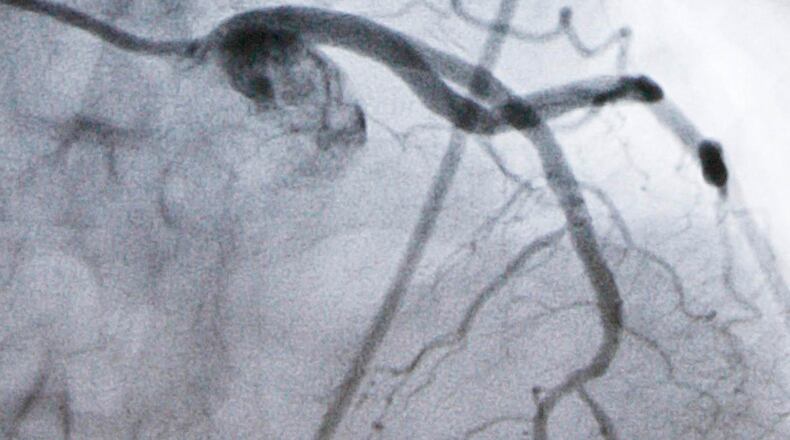

Heart disease is the nation’s leading cause of death and high LDL cholesterol, which causes plaque to build up in arteries, is a top risk factor for heart attacks and strokes. While an LDL level of 100 is considered fine for healthy people, doctors recommend lowering it to at least 70 once people develop high cholesterol or heart disease — and even lower for those at very high risk.

Statin pills like Lipitor and Crestor, or their cheap generic equivalents, are highly effective at lowering LDL. For additional help, some powerful injected drugs work differently, blocking a liver protein named PCSK9 that limits the body’s ability to clear cholesterol from blood. Yet only a small fraction of people who could benefit from PCSK9 inhibitors use them. While prices for the costly shots have dropped recently, patients still may dislike administering shots and Navar said they’re more complex for doctors to prescribe.